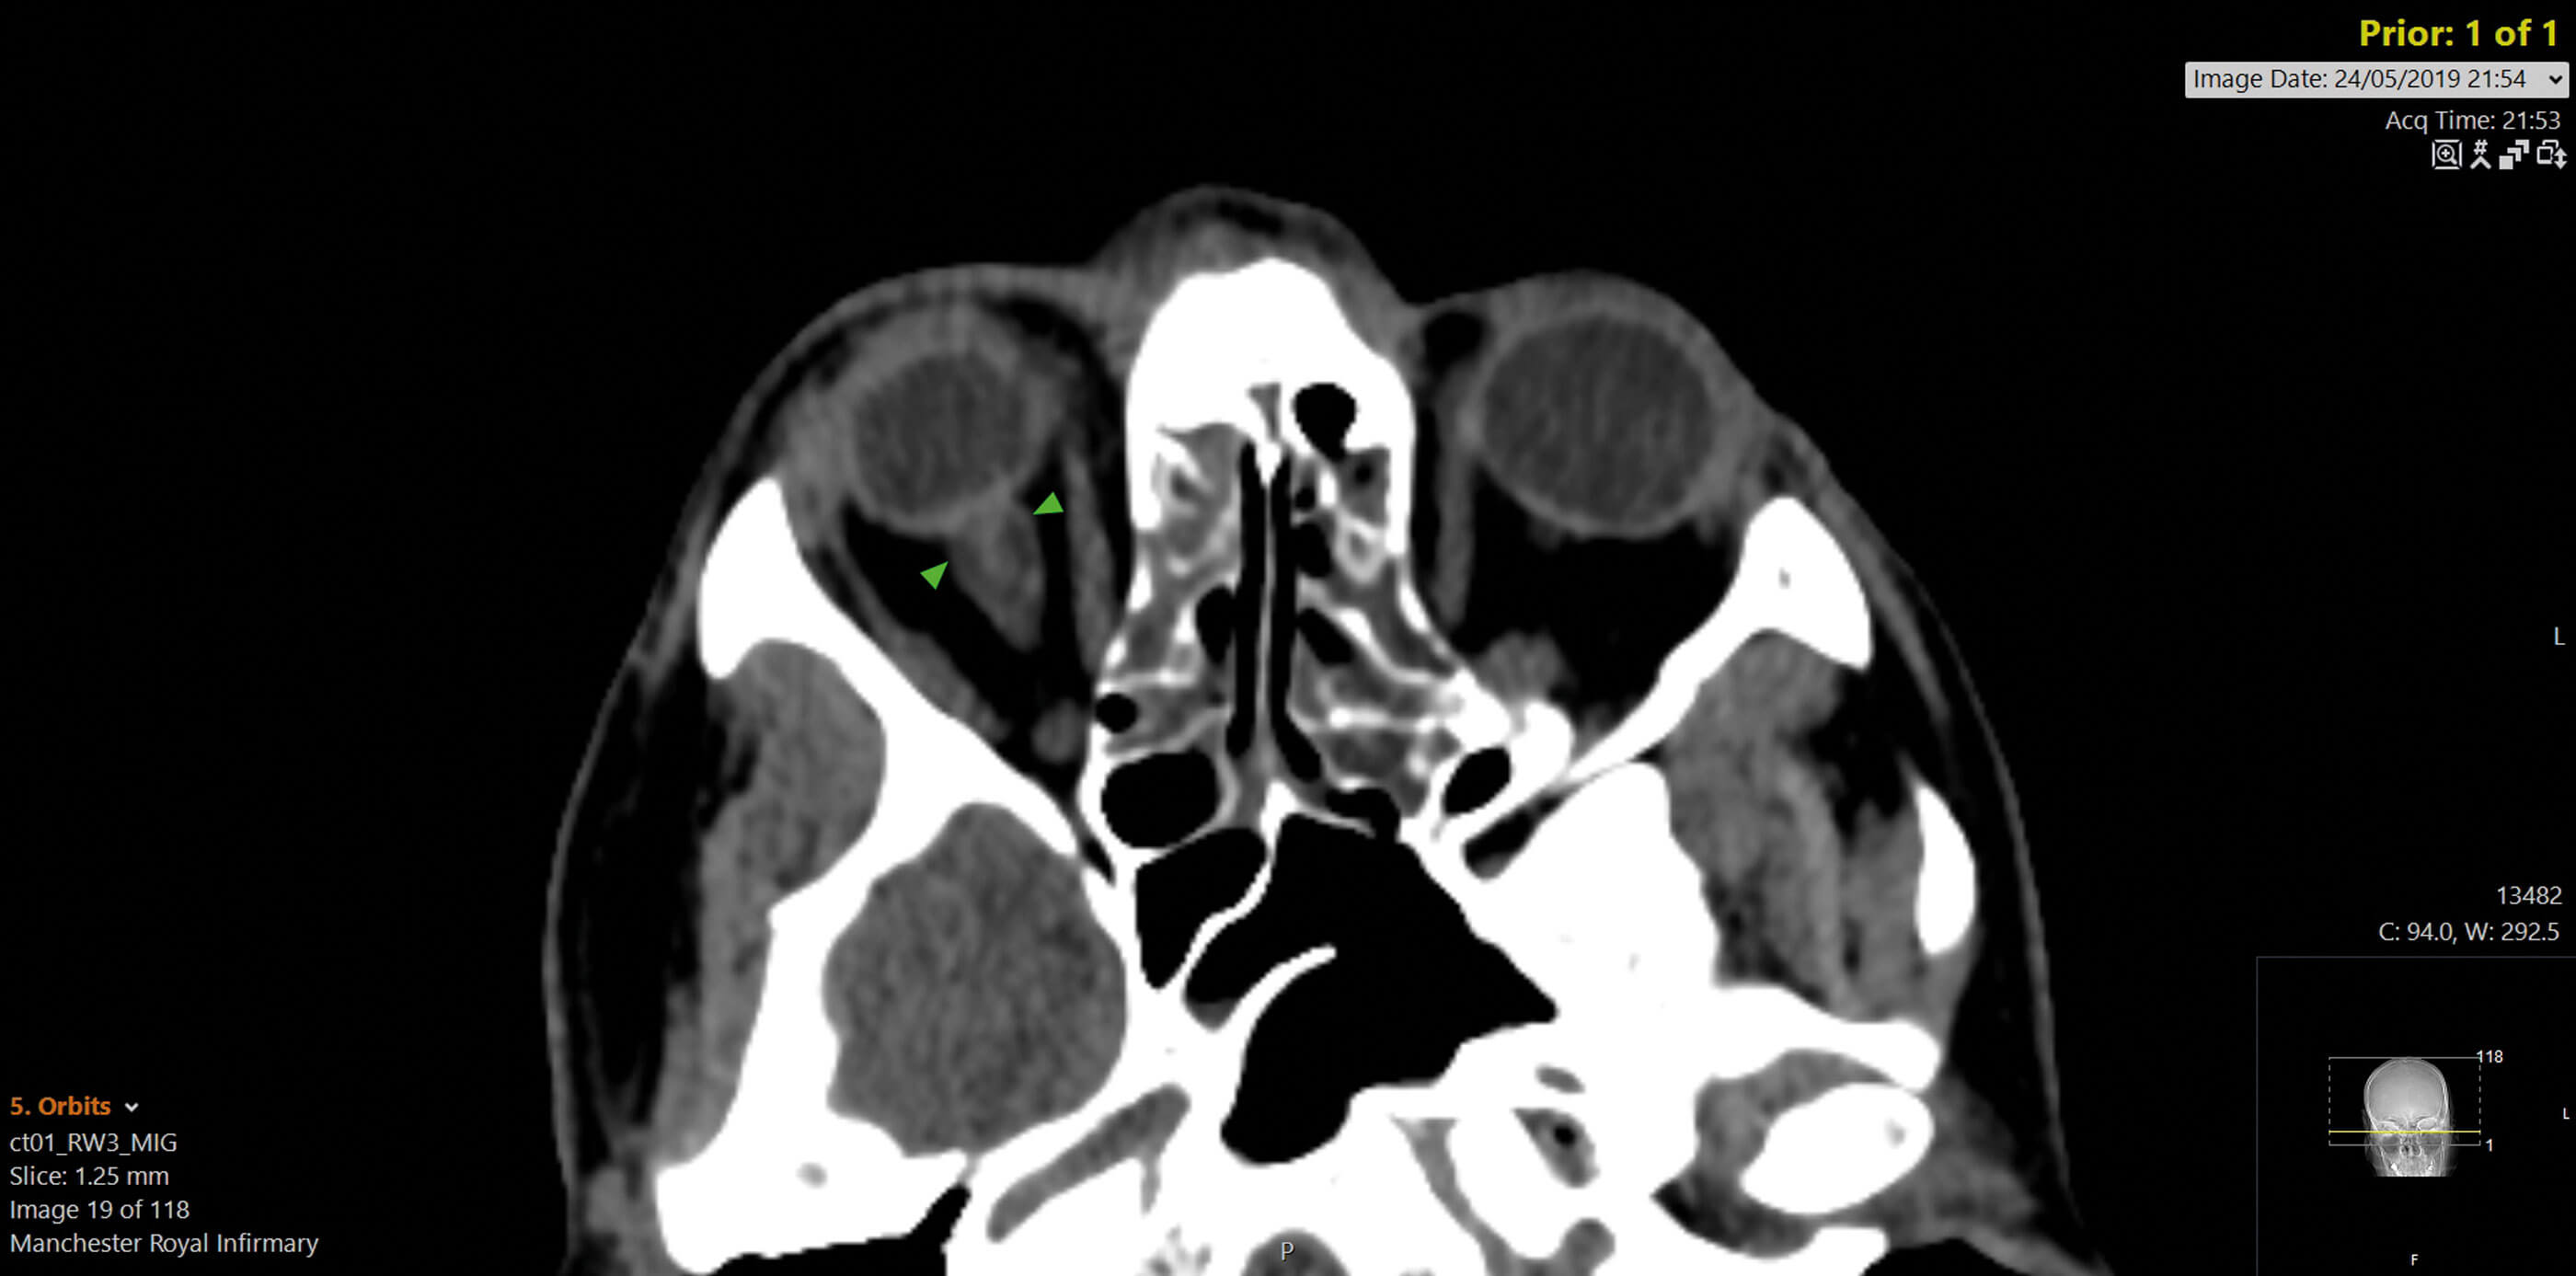

Figure 3: CT head showing dilatation of optic nerve.

Tumour, hypotony, inflammation and retrobulbar mass were excluded. The appearance of the optic discs raised suspicion for grade one papilloedema bilaterally. He was urgently referred to the medical team, where a computed tomography (CT) scan revealed evidence of chronic raised intracranial pressure with dilatation of the optic nerve sheaths (Figure 3) and an empty sella. Lumbar puncture demonstrated raised opening pressure with normal cerebrospinal fluid (CSF) composition. He was eventually diagnosed with idiopathic intracranial hypertension and managed medically with success.